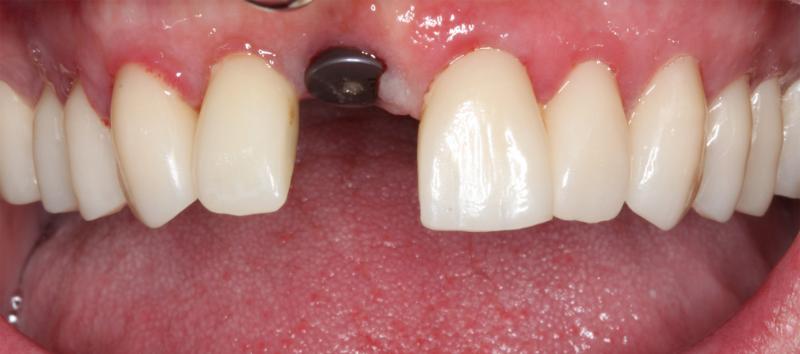

A dental implant is a small titanium post that is surgically placed into the jawbone, providing a foundation for a replacement tooth or teeth. Placing an implant is a common surgical procedure performed by our highly trained prosthodontist.

A bone graft may be needed in cases where your jawbone has deteriorated or is too thin to support a dental implant. A bone graft helps strengthen your jawbone and provides a solid foundation for the implant.

The implant process can vary depending on your individual needs and circumstances. In most cases, we can plan, create, and place your implants from start to finish in just one day!